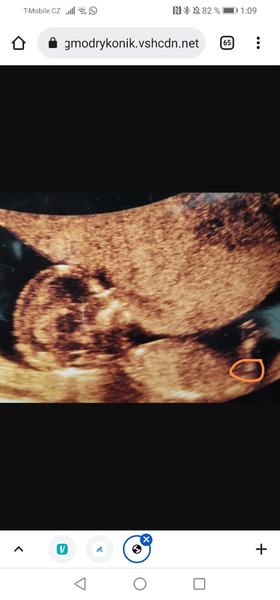

@nataliekustova co byste rekly holky tady? Vidite neco?

@adrizojka holka? Dajte vedieť či som tipla správne 😀🙏

@simonabaa asi taky holka, ale nie som si istá či to nezakrýva noha 😀, dajte pak taky vedieť ☺️👍